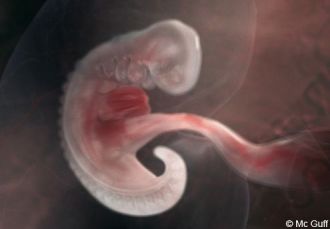

6 SA / 4 SG

La 4e semaine de grossesse correspond à 6 SA (semaines d’aménorrhée). Ce premier trimestre est primordial pour le développement embryonnaire. De votre côté, vous savez que vous êtes enceinte mais personne ne le voit…

Côté bébé

L’embryon mesure entre 2 et 4 millimètres. Son poids est encore négligeable.

Son développement à 4 semaines de grossesse :

De crevette, l’embryon devient hippocampe : il s’allonge encore. Sa tête devient plus proéminente et il semble réellement posséder une queue. Pour l’instant, il n’a pas d’excroissance pour les jambes. On remarque également des pulsations, c’est le premier « rythme cardiaque » ! Bien sûr, le cœur de l’embryon n’est pas encore vraiment formé. Il possède seulement deux chambres (au lieu de quatre, à terme).

A ce stade, le système le plus avancé est le système nerveux central : le tube neural est désormais formé et, à son extrémité, le cerveau est en formation (c’est pour cela que la tête semble si grosse). Le foie va commencer à apparaître, avant le reste du système digestif. A ce stade, l’embryon est nourri par le corps jaune (résidu de l’ovulation) en attendant que le placenta soit formé.